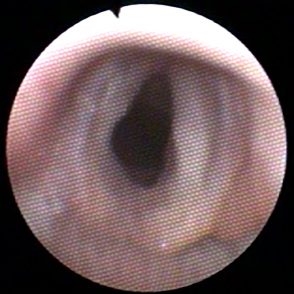

Voor alle andere oorzaken kan onder andere een scoop nodig zijn. Hiermee kan in de luchtpijp (trachea) en een stuk van de vertakkingen (bronchiën) gekeken worden, oftewel een tracheobronchoscopie. Daarnaast is het mogelijk om biopten te nemen of spoelingen te doen. Zo’n spoeling of lavage kan gebruikt worden voor cytologisch onderzoek en voor bacteriologisch onderzoek.